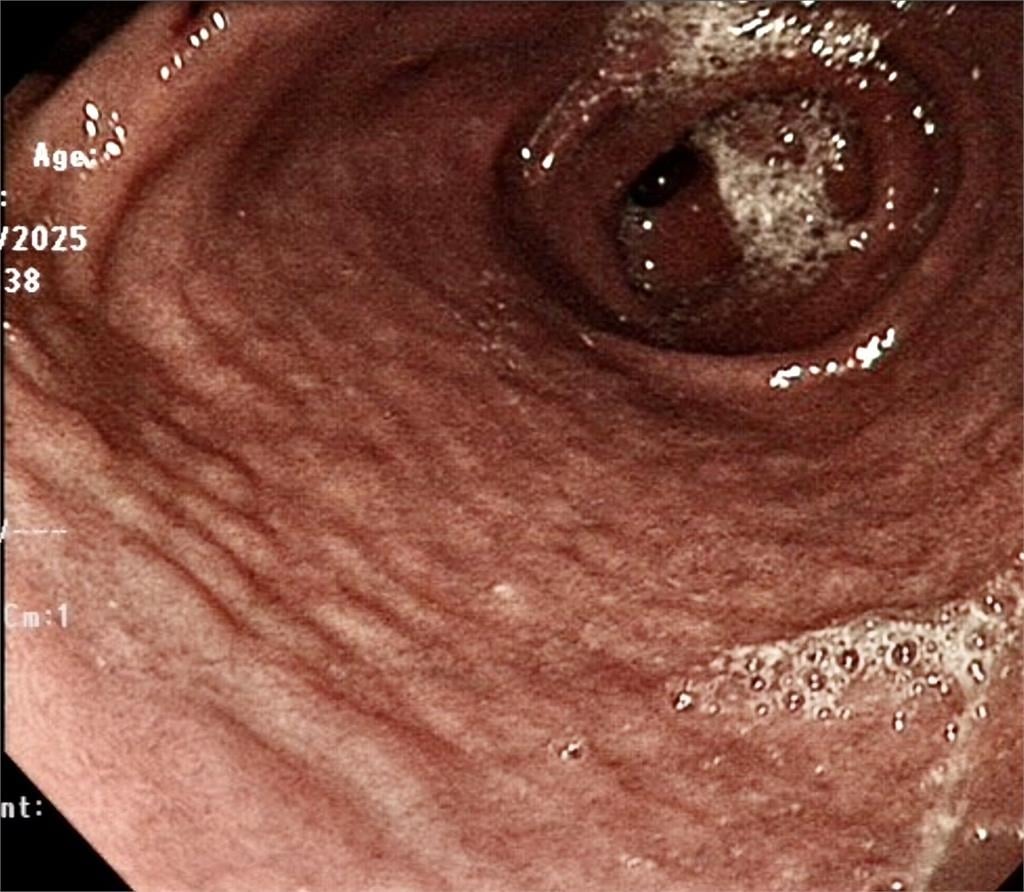

生活中心/楊佩怡報導一名孩童近期因嚴重吐血緊急住院,沒想到在做胃鏡檢查時,醫師發現男孩的胃黏膜上布滿了一顆顆像是「鵝卵石」的突起物。切片證實感染幽門螺旋桿菌(H. pylori)。更令人揪心的是,病理報告顯示已出現「細胞異形增生」(low grade dysplasia),即所謂的癌前病變。

一名孩童近期因嚴重吐血緊急住院,沒想到在做胃鏡檢查時,醫師發現男孩的胃黏膜上布滿了一顆顆像是「鵝卵石」的突起物。切片證實感染幽門螺旋桿菌(H. pylori)。更令人揪心的是,病理報告顯示已出現「細胞異形增生」(low grade dysplasia),即所謂的癌前病變。